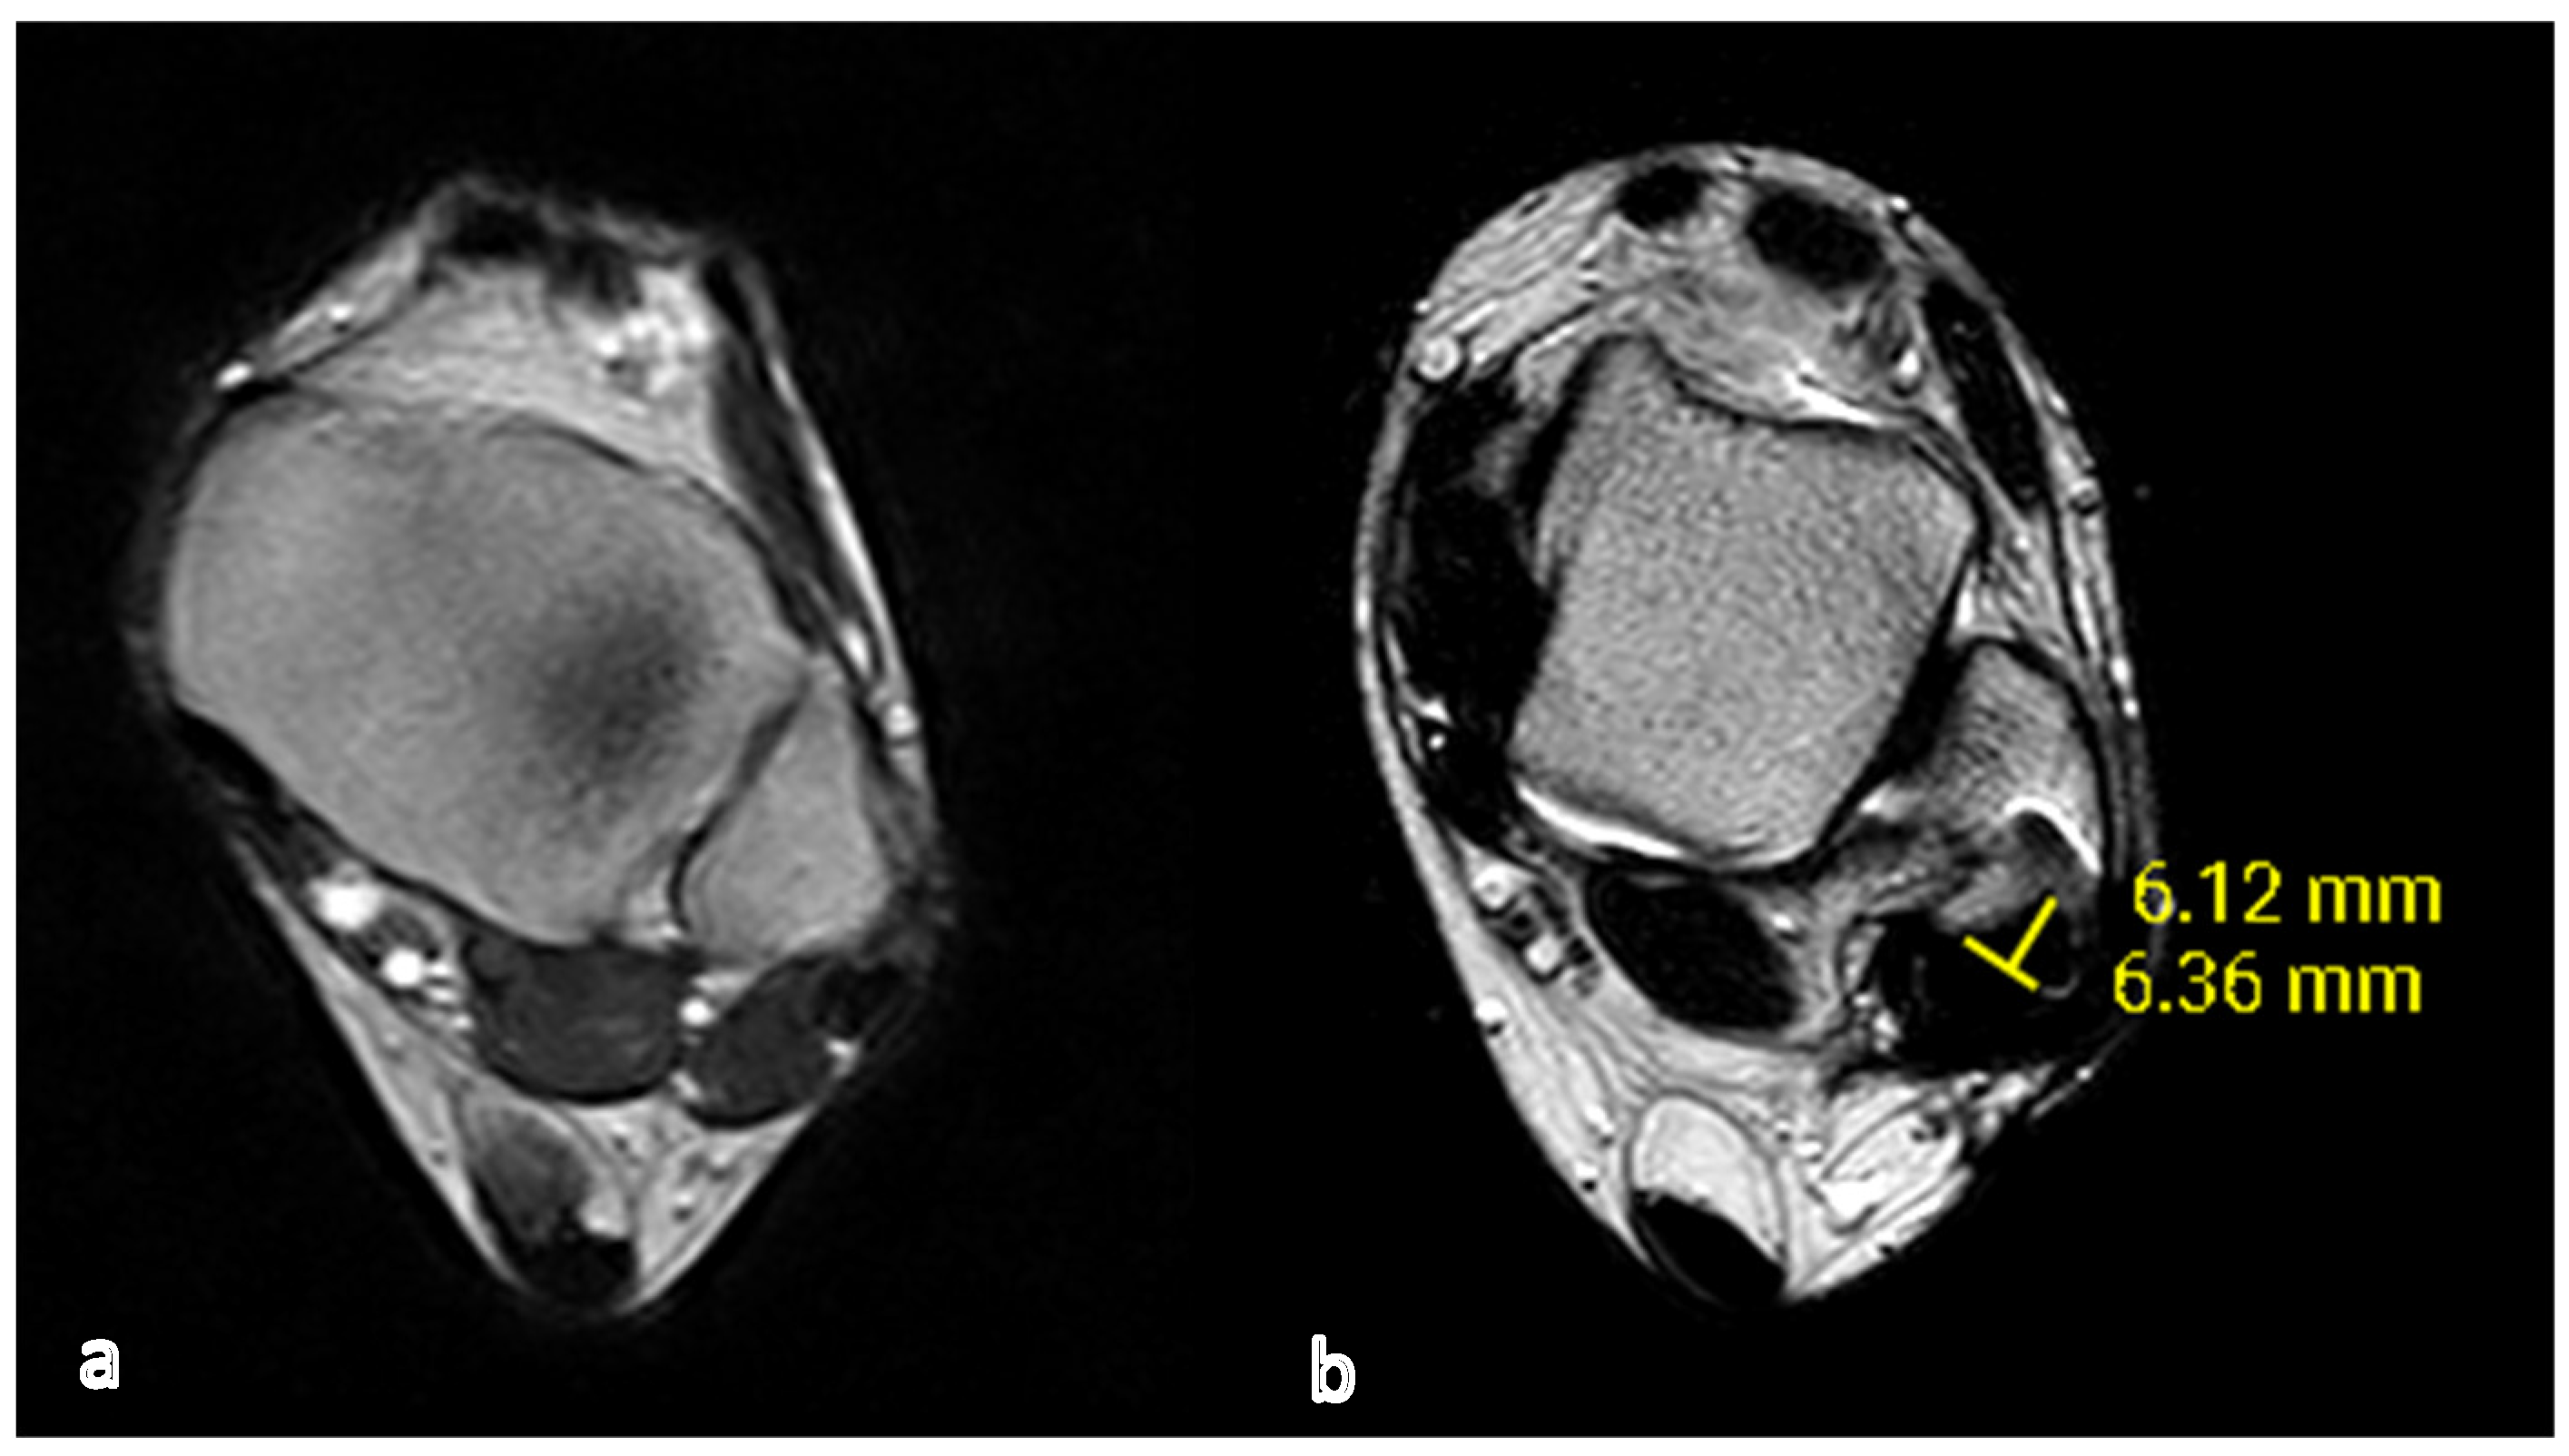

Fibular groove morphology and measurements on MRI correlation with fibularis tendon Fibular Groove Deepening Technique this technique article describes a fibular groove deepening with preservation of the fibrocartilage in. this technique article describes a fibular groove deepening with preservation of the fibrocartilage in conjunction with repair of the superior peroneal retinaculum. we discuss both direct and indirect groove deepening procedures (both involving some form of a “fibular. (1) anatomic reattachment of the. Fibular Groove Deepening Technique.

Fibular groove morphology and measurements on MRI correlation with fibularis tendon Fibular Groove Deepening Technique diagnosis is made clinically with subfibular ankle pain with the sensation of apprehension or subluxation with active dorsiflexion. there are five categories of surgical repair: this technique article describes a fibular groove deepening with preservation of the fibrocartilage in conjunction with repair of the superior peroneal retinaculum. this technique article describes a fibular groove deepening with. Fibular Groove Deepening Technique.